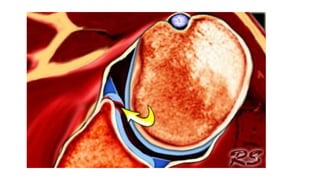

• Hill – sach’s lesion – impaction

fracture on humeral head on

posterolateral aspect can be

produced as the shoulder is

dislocated due to impaction of

humeral head against glenoid rim

• Instability results when the defect

engages the glenoid rim in the

functional arc of motion at 90

degrees abduction and external

rotation

• defects of 35% to 40% of head

were shown to decrease stability,